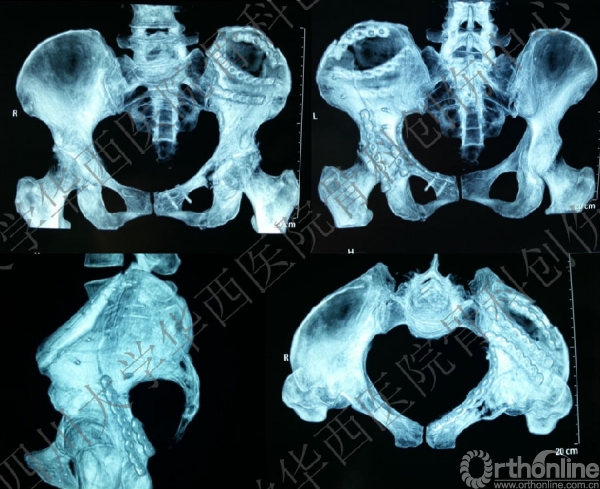

术后X线片

这是术后的X线片,患侧正位、髂骨斜位、闭孔斜位。

术后三维重建

术后三维重建前面观完美!

术后三维重建后面观,发现后壁的骨折有明显的移位,后脱位的风险增加,我们决定!

3天后

3天后,行后路切开复位内固定术。